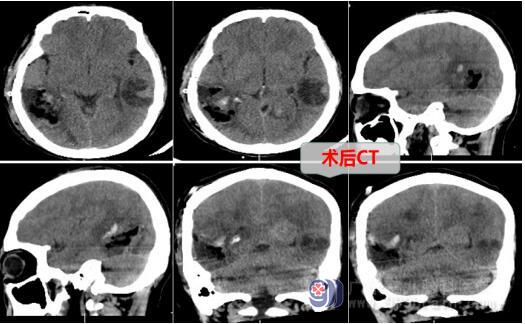

欧阳辉教授结合患者的临床症状和检查结果,考虑为肺癌脑转移瘤。神经外十科医疗团队经过讨论后,决定为患者实施手术切除颅内的肿瘤,术中肿瘤成功切除,病理结果提示为右侧颞枕叶转移瘤-考虑肺腺癌转移。术后,患者还需要针对肺癌原发灶等进行综合治疗。